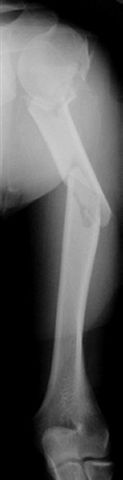

Re: Многооскольчатый перелом плеча

Although we can not see exactly the head piece, and assuming that there are not signs of infection, my suggestion would be to do some type of "bridging" procedure : implant fixation in head piece and distal main fragment, and the rest to be left on its soft tissue attachments (living bone graft).

I just did this attached case, using 90 degrees angled blade plate, and this would be my preference in all similar cases.

Two days ago, I had to plate TWO humeral NONUNIONS after intramedullary nailing. Just to remove them from proximal end, significant damage had to be done to the rotator cuff. My belief is (and supported by the most of recent literature) is that the plating is a better option for humeral fractures.